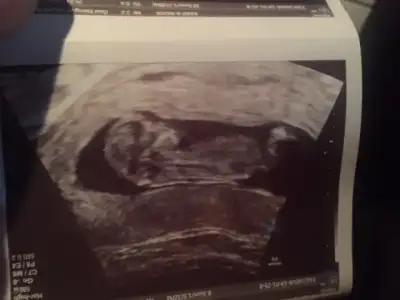

8 haftalık görüntü tahmin alabilirmiyim

• 5DF6B3C7-374F-4E15-913C-1AB0BFEC0082.webp

5DF6B3C7-374F-4E15-913C-1AB0BFEC0082.webp

12,9 KB · Görüntüleme: 95